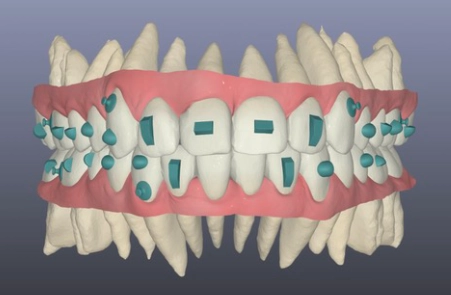

Hinter jeder erfolgreichen Aligner-Behandlung steht ein digitaler Plan. Mit modernster 3D-Technologie und gelenkzentrierter Diagnostik planen wir Ihre Zahnbewegungen präzise nach unserem Konzept KFO360° — noch bevor der erste Aligner gefertigt wird.

Wir kombinieren hochauflösende 3D-Scans mit Kiefergelenksdiagnostik, um eine Behandlung zu entwerfen, die zu Ihrem gesamten Kauapparat und Körper passt.

Wir scannen Ihre Zähne, messen ihr Knochenangebot und Ihre Kiefergelenksachse mit höchster Präzision.

Expertengeführte Bewegungssimulation

Jede Zahnbewegung planen wir selbst — nicht die Aligner-Firma. Weil wir den Patienten kennen, passt jeder Schritt genau.